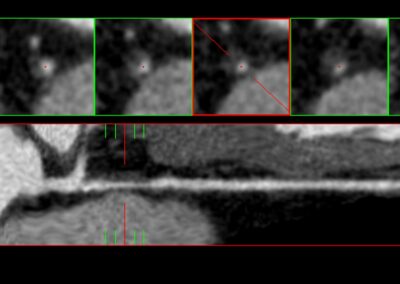

Τρισδιάστατη και δισδιάστατη απεικόνιση των στεφανιαίων αγγείων όπου διακρίνεται σημαντική στένωση λίγο μετά την έκφυσή του πρόσθιου κατιόντα κλάδου